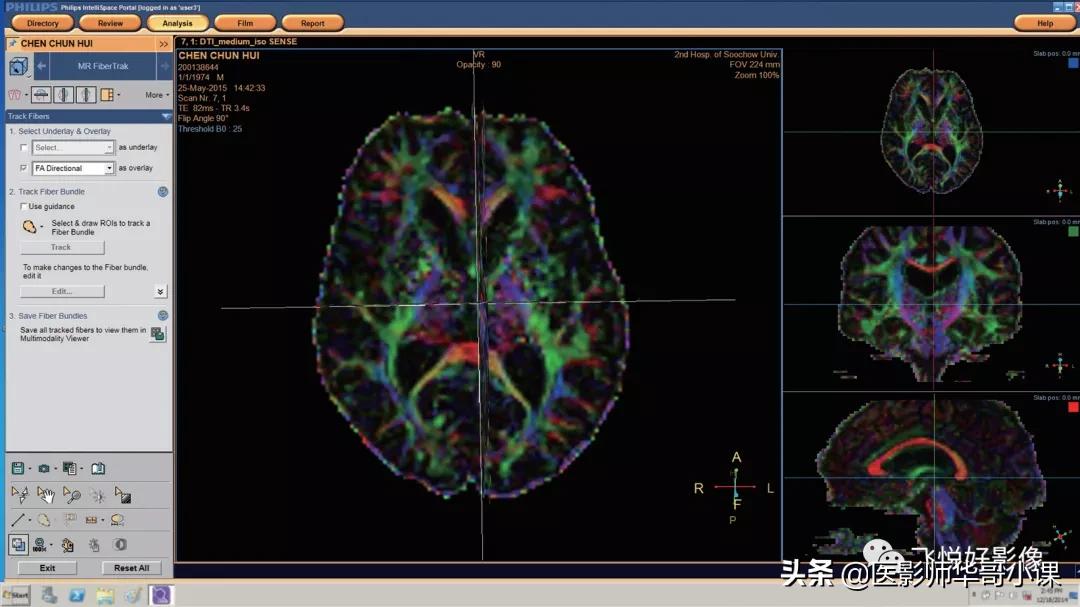

DTI后处理

至少有 6 个方向的弥散及至少 2 个 b 值方可进入此步骤。鼠标左键点击向右箭头(图11)进入DTI处理步骤。

进入DTI后处理界面,如图12所示

图12.DTI后处理界面

第一步,选择叠加底层

如需选择底层或叠加图,请在前方小方块内打勾,即可在后方选择底图或叠加层,常用3D序列作为底图。

第二步,定义纤维束( Fiber)

选择 Use guidance,以激活 DTI 指南,这将在主视窗的右侧显示使用指南,此指南在列表中可选择不同纤维束的自定义方法,可引导用户进行 DTI 分析。

图19.Track Fiber Bundle